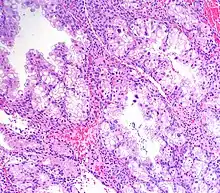

Micrograph showing Arias-Stella reaction in endometrium

Arias-Stella reaction, also Arias-Stella phenomenon, is a benign change in the endometrium associated with the presence of chorionic tissue.[1]

Arias-Stella reaction is due to progesterone primarily. Cytologically, it looks like a malignancy and, historically, it was diagnosed as endometrial cancer.[1]

It is significant only because it can be misdiagnosed as a cancer. It may be seen in a completely normal pregnancy.

It is characterized by nuclear enlargement and may also have any of the following: an irregular nuclear membrane, granular chromatin, centronuclear vacuolization, and pseudonuclear inclusions.[1]